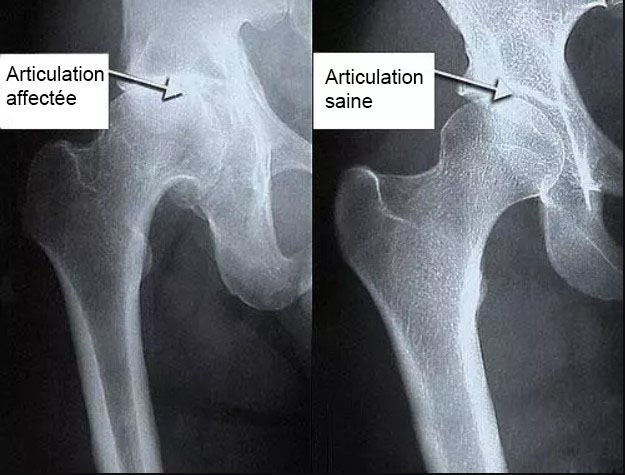

Traitement de l'articulation de la hanche d'un patient âgé de 44 ans. La douleur atroce qui a torturé le patient pendant 2 ans, a été complètement guérie :